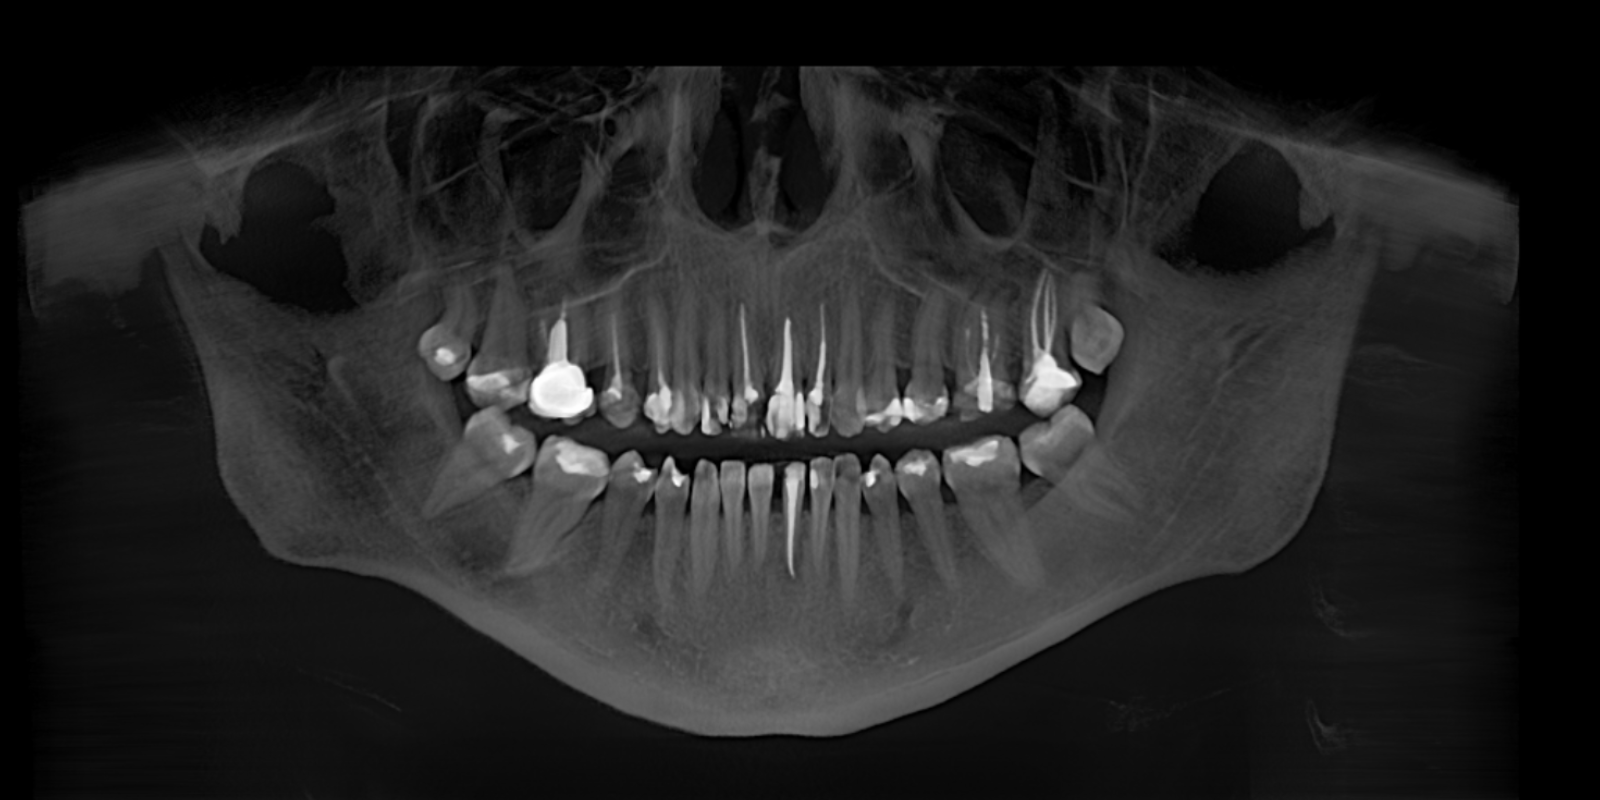

На первый взгляд казалось, что достаточно просто заменить старые пломбы. Но во время диагностики мы заметили и другие детали: смещение средней линии, компрессию (скученность) в области правых боковых зубов, значительное разрушение передних зубов.